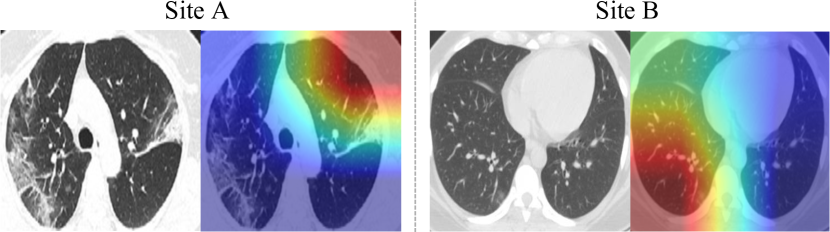

Refer to caption

Figure 5: Visualization of color maps of failure cases with Grad-CAM [41].

To understand the behavior of our framework, we observe the Grad-CAM [41] visualization results on the two heterogeneous sites, as saliency maps (shown in Figure 4). It is consistently observed on both datasets that the suspicious lesion regions are successfully localized across various abnormality patterns (e.g., bilateral and peripheral ground-glass, and consolidative pulmonary opacity), even with quite mild lesions. This analysis reveals promising interpretability of our classification model trained with image-level labels, demonstrating potential clinical relevance for COVID-19 image-based computer-assisted diagnosis. In addition, we present typical failure cases in Figure 5. We see that the method would mis-classify samples due to wrongly attended regions, and fail to distinguish images with unobvious lesions.